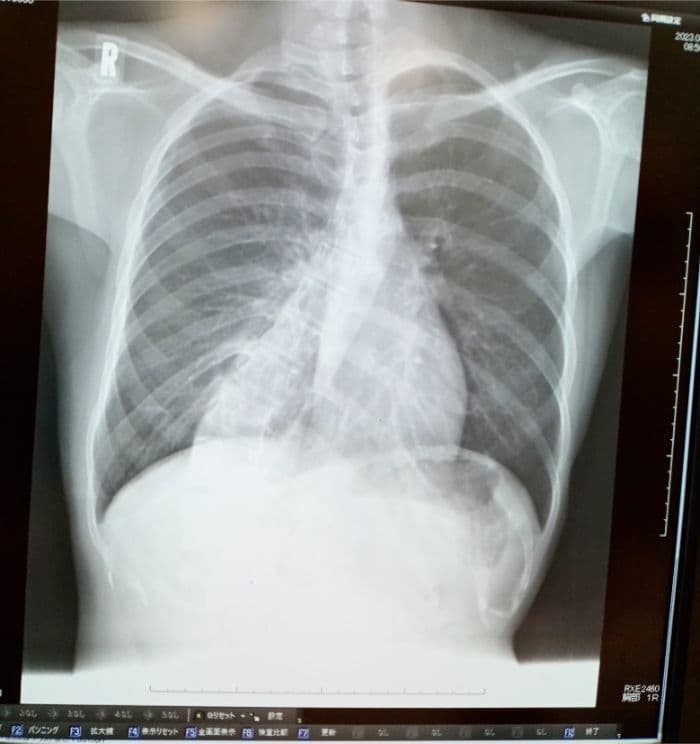

側弯による「見た目」が気になる方へ

側弯の見た目は、骨だけで決まって

いるわけではありません。

背中のふくらみ、左右差

服を着たときの違和感。

これらは、椎体回旋などの

構造的要因に加え

筋・筋膜の緊張、姿勢保持

呼吸や荷重バランスが重なって

強調されている場合があるので